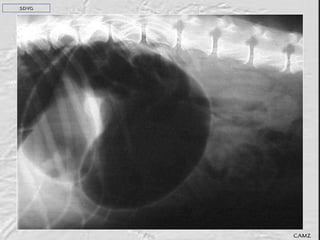

Radiografía lateral derecha: estómago dilatado con gas y dividido en  dorsal (píloro distendido) y ventral (fundus y cuerpo) por una línea de tejido blando. Vísceras distendidas sugestivo de íleo . SDVG CAMZ

SDVG CAMZ